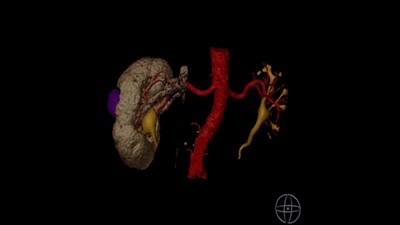

Чрескожная нефролитотрипсия

Оперирует Сорокин Николай Иванович.